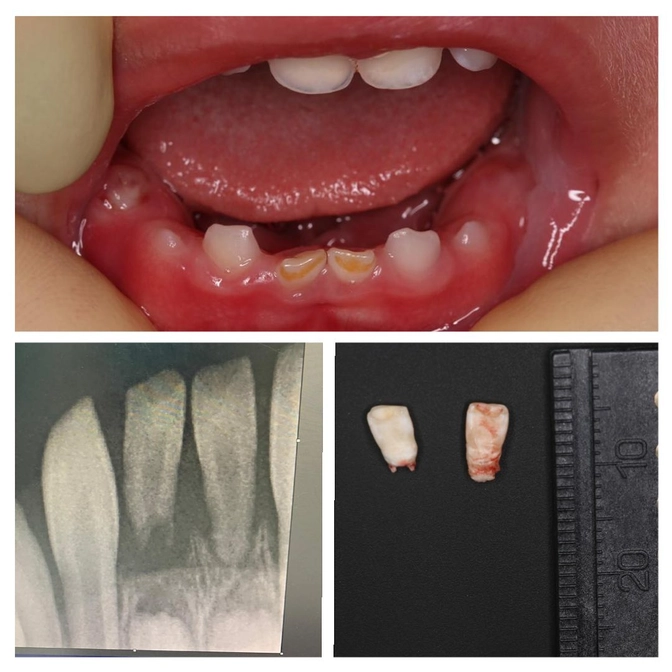

Такие маленькие сами по себе или кариес "съел", или стерлись?

Малышу 1,8 года.

Родился он УЖЕ С ЗУБАМИ.

Да, вот эти два мелких зубика - натальные, т.е. появившиеся у ребенка еще в утробе матери.

Родители решили обратиться в #ЦентрСелютиной, потому что появилась небольшая подвижность и полоски на зубах.

Оба зубика решено удалить.

Работу проводила детский стоматолог Светлана Кожемякина.

Понадобилась всего лишь аппликационная анестезия - помазать десны в области удаляемых зубов специальным замораживающим гелем.

При необходимости делают рентген, т.к. часто эти зубы не имеют корней.

Такой зуб удерживается только тканями десны и очень подвижен.

В любой момент он может выпасть, поэтому его удаляют, чтобы малыш случайно им не подавился.